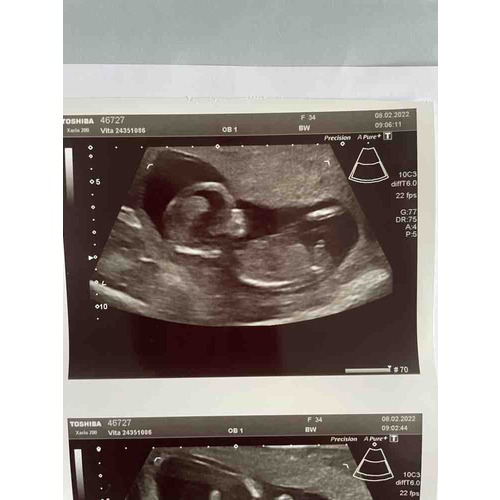

Goedemorgen @nubster; bij deze nog een tweede foto. Ben benieuwd of het zichtbaar is 😊

Zo benieuwd of hier iets op te zien is bij 13.3? Zelf kan ik er niets van maken. Hopelijk @nubster wel🙂.

Goedemorgen, gisteren echo gehad bij 12+0; enig idee? Ik kan er niks van maken zelf..

En de andere echo